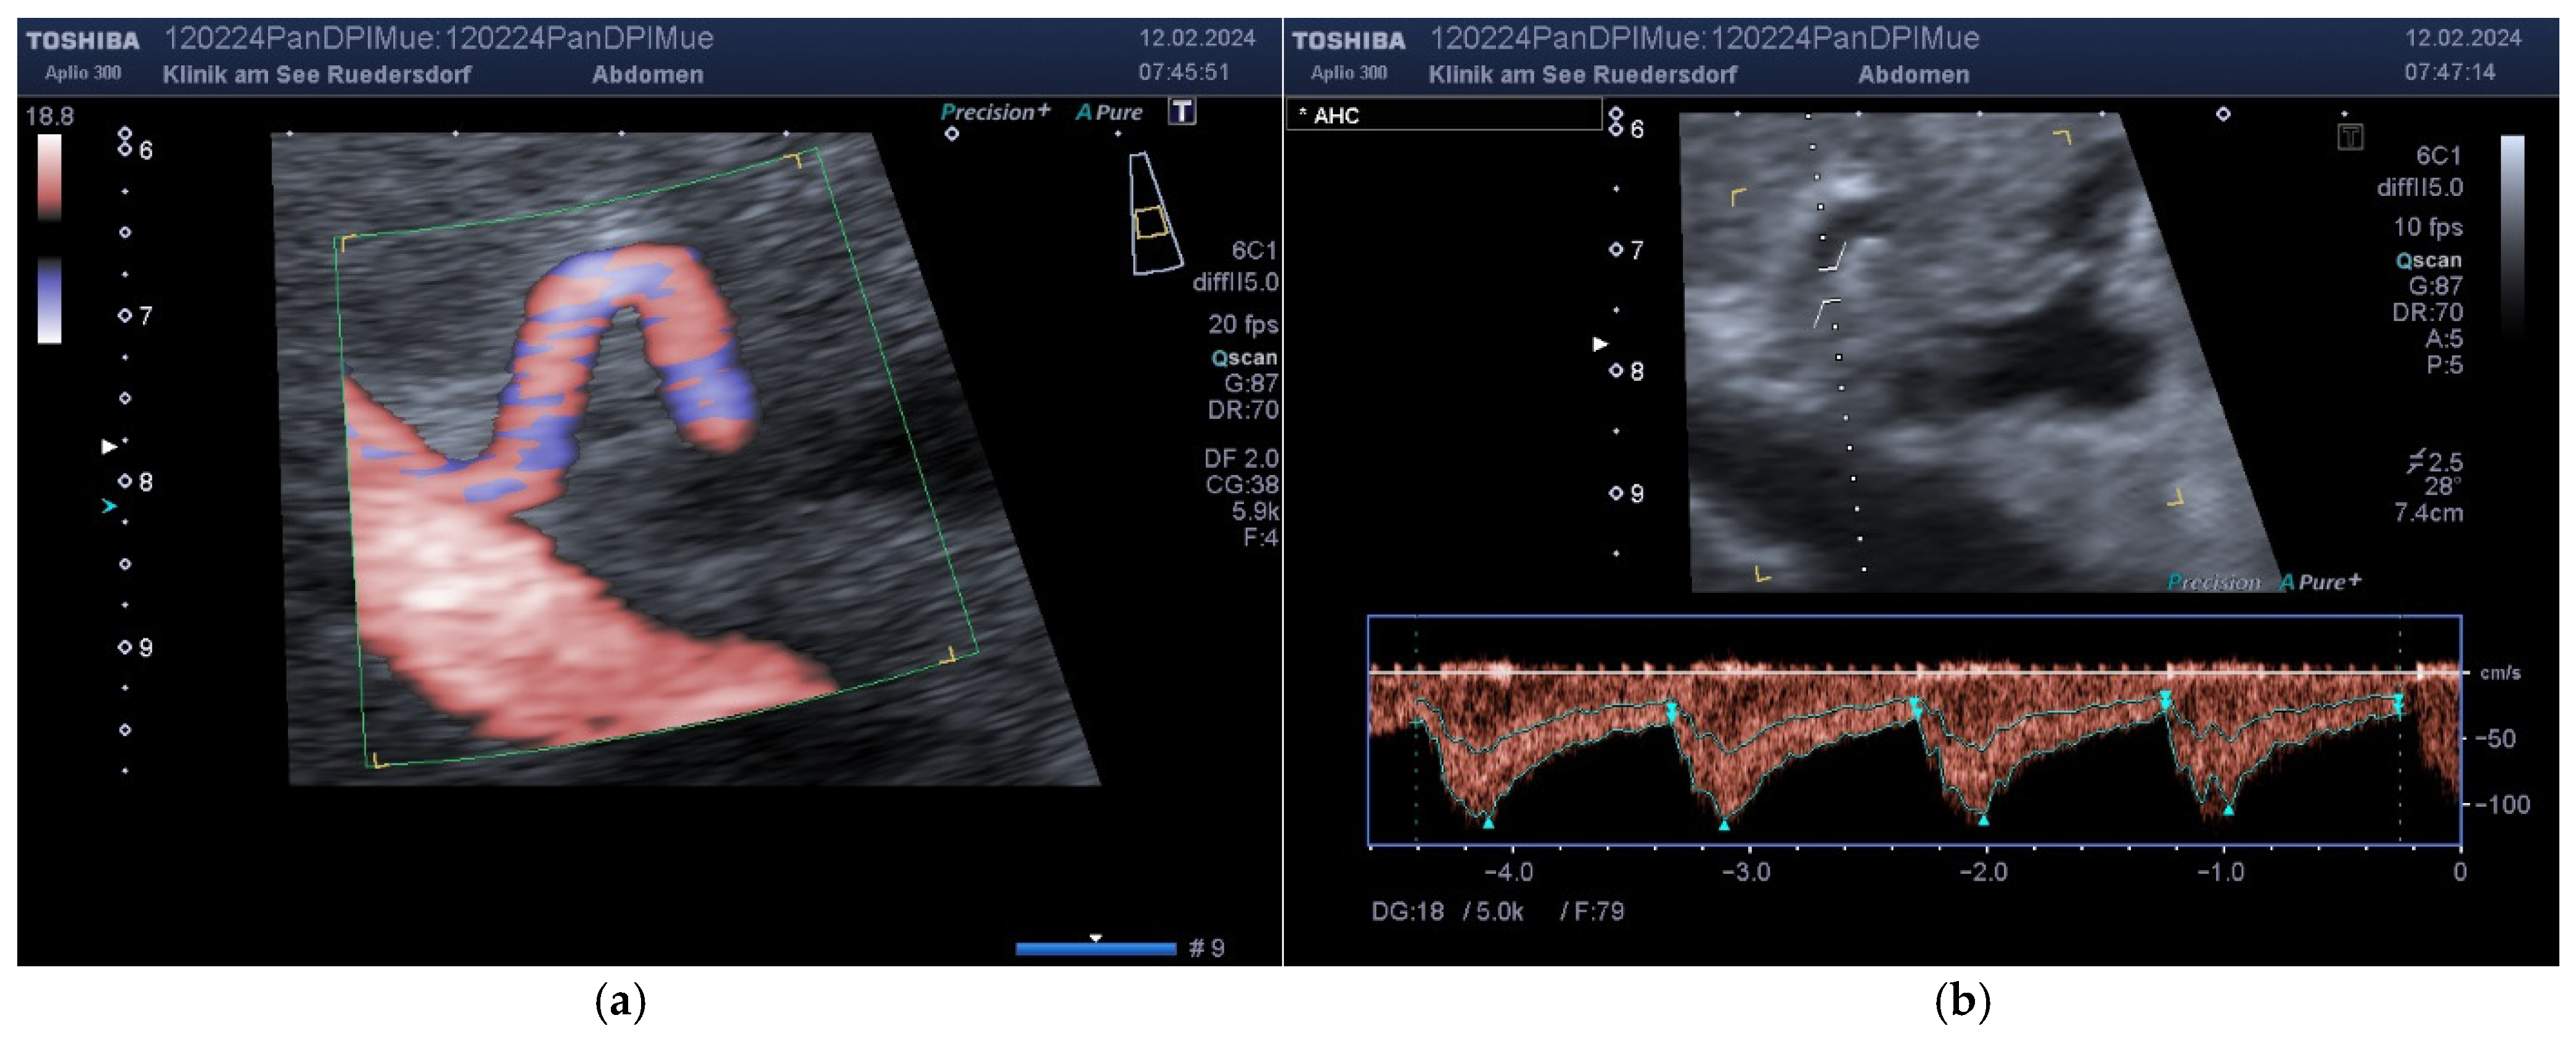

2.3.1. Determination of Vessel Diameter

2.3.2. Location of the Probe, Insonation Angle, and Doppler Window